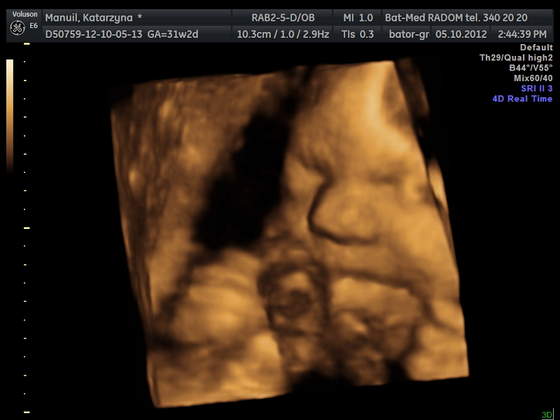

Byłam z Mamą i Mężem i wszyscy troje mieliśmy łezki w oczach jak zobaczyliśmy Młodą na 4D:)

pozdrawiamy :) z uśmiechem Jasi: ---> uśmiech Jasi

Mąż twierdzi, , że Jasia na ostatniej fotce, złości się identycznie jak ja ;)

• 1.jpg

1.jpg

23,5 KB · Wyświetleń: 44

• manuil katarzyna_10.jpg

manuil katarzyna_10.jpg

20,2 KB · Wyświetleń: 91